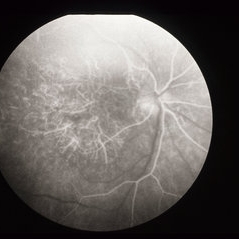

ARMD

Jan 13 2014 by David Callanan, MD

HM OU marked RPE atrophy, 63-year-old female.

Condition/keywords: age-related macular degeneration (AMD)